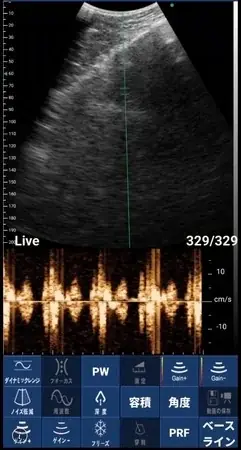

「ポケマム・サウンズ」は、スマートフォンと接続することで、妊婦が自宅でお腹の中の赤ちゃんの姿をリアルタイムで確認できるだけでなく、赤ちゃんの心音も聴くことができるという画期的なデバイスです。この機能により、妊婦は胎児の様子を見ながら心音を聴くことで、より深く妊娠を実感し、不安を軽減することが期待されています。

• 胎児の映像をリアルタイムで表示

• 胎児心音の聴取(専用アプリ連携)

スキャンモード B、B/M、B+カラー、B+PDI、B+PW

プローブ周波数 3.2MHz/4MHz

スキャン深度 90/160/200/240mm